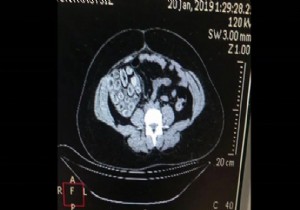

Ekipler yapılan aramada A.D.S.L.'nin uyuşturucu maddeyi kapsül halinde yutmuş olabileceğini değerlendirerek Haseki Eğitim ve Araştırma Hastanesine sevk etti. Hastanede sindirim sistemi röntgen filmi çekilerek kontrol edilen Brezilya uyruklu kadın A.D.S.L.'nin içinde kokain bulunan kapsül şekline soktuğu 115 prezervatifi yuttuğu belirlendi.